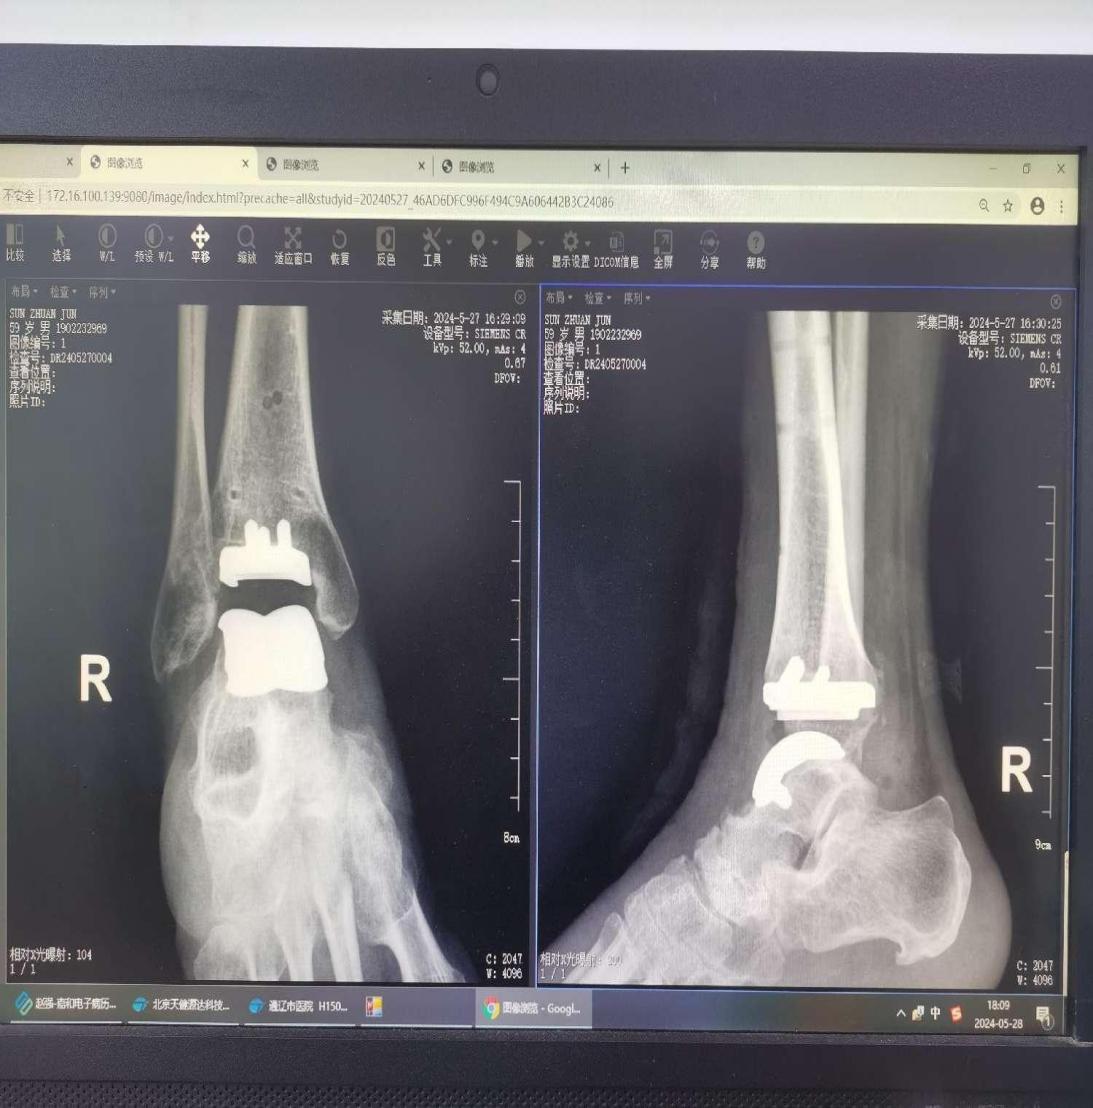

入院后,胡中申主任医师带领其关节外科团队对该病例进行详细周全地讨论。由于患者右侧踝关节骨性关节炎严重,经关节镜手术治疗无效,综合评估患者病情后,胡中申主任带领徐宏顺副主任医师、陈哲医师对患者采用“3D打印辅助下右侧全踝关节置换术”进行治疗。术后患者右踝关节疼痛明显缓解,功能良好。次日可扶双拐进行行走功能锻炼,CMFS评分90分。

术后X线检查